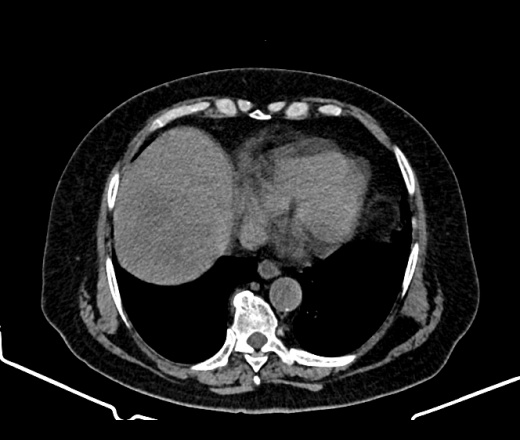

МТС печени? инвагинация?

Здравствуйте подскажите, женщина 77 лет, жалобы на боли в правом подреберье, в печени это мтс? и инвагинация ли справа?